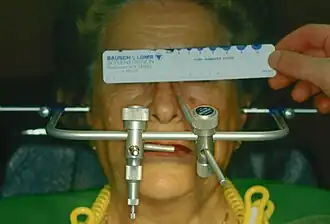

Übertragungsbogen

Mit Hilfe eines Übertragungsbogens wird die kiefergelenksbezogene Montage der Arbeitsmodelle im Artikulator (einem Kausimulator) ermöglicht. Ohne das Anlegen eines Gesichtsbogens müssen die Gipsmodelle nach Mittelwerten in einem Mittelwertartikulator montiert werden. Diese Artikulatoren orientieren sich am Mittelwert des Bonwill-Dreiecks. Dieses wird gebildet vom Kontaktpunkt der unteren mittleren Schneidezähne und vom Mittelpunkt der Kondylen (Kiefergelenksköpfchen des Unterkiefers). Zur Kauebene bildet dieses Dreieck den Balkwill-Winkel, der im Mittel zwischen 20° und 25° liegt. Mit Hilfe des Gesichtsbogens ist eine Individualisierung dieses Winkels und des Bonwill-Dreiecks möglich. Das Gipsmodell des Oberkiefers kann schädelbezogen in den Artikulator montiert werden. Je nach Artikulatorsystem erfolgt die Positionierung des Gesichtsbogens am Patienten entweder an der Frankfurter Horizontale oder der Camperschen Ebene. Die Frankfurter Horizontale verläuft durch den Unterrand der Orbita (Augenhöhle) und den Oberrand der beiden Pori acustici externi (äußere knöcherne Ohröffnung). Die Campersche Ebene verläuft durch die Spina nasalis anterior (unterer Dorn an der vorderen knöchernen Nasenöffnung) und den Oberrand des Porus acusticus externus beidseits. Die Campersche Ebene verläuft annähernd parallel zur Kauebene. Die Individualisierung des Artikulators soll sich vorteilhaft auf die Herstellung der statischen Okklusion (Schlussbiss) auswirken, woraus weniger nachträgliche Korrekturen des Kaureliefs durch Einschleifen notwendig werden.[20]

Gesichtsbogen

-

Anlegen eines Übertragungsbogens

Anlegen eines Übertragungsbogens